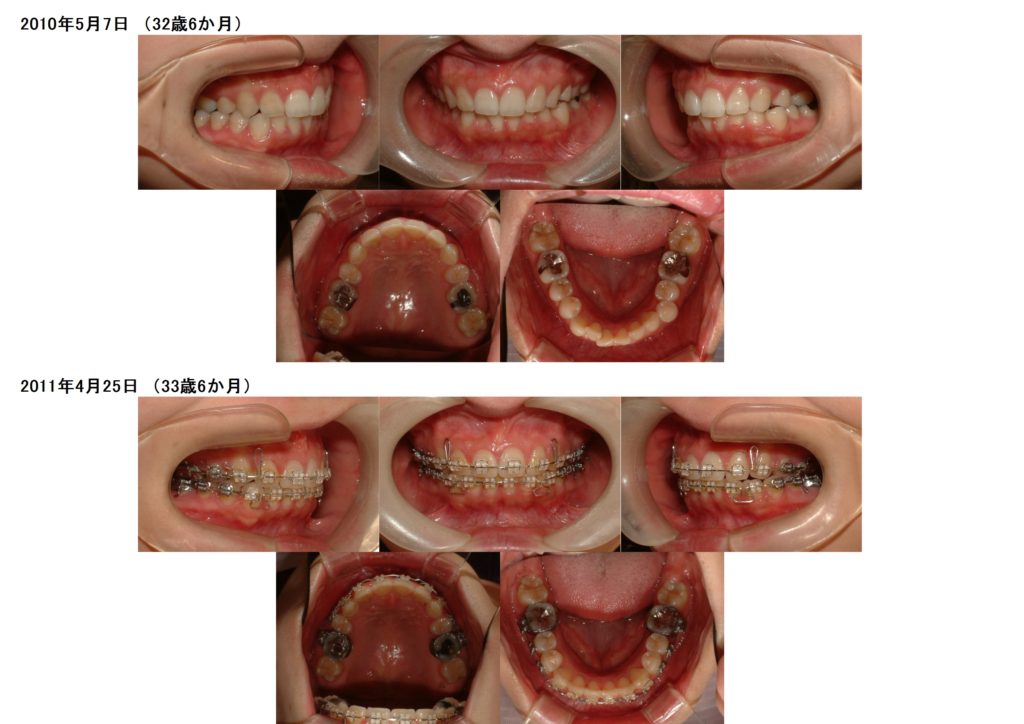

口腔内写真がしっかり撮れていると、治療の進行具合も分かり易いですし、撮り方によっては全然分からないこともあります。

上下の口腔内写真を見比べても同じ角度や口腔内の大きさが統一されていると、パッと見ればすぐ分かりますよね☆